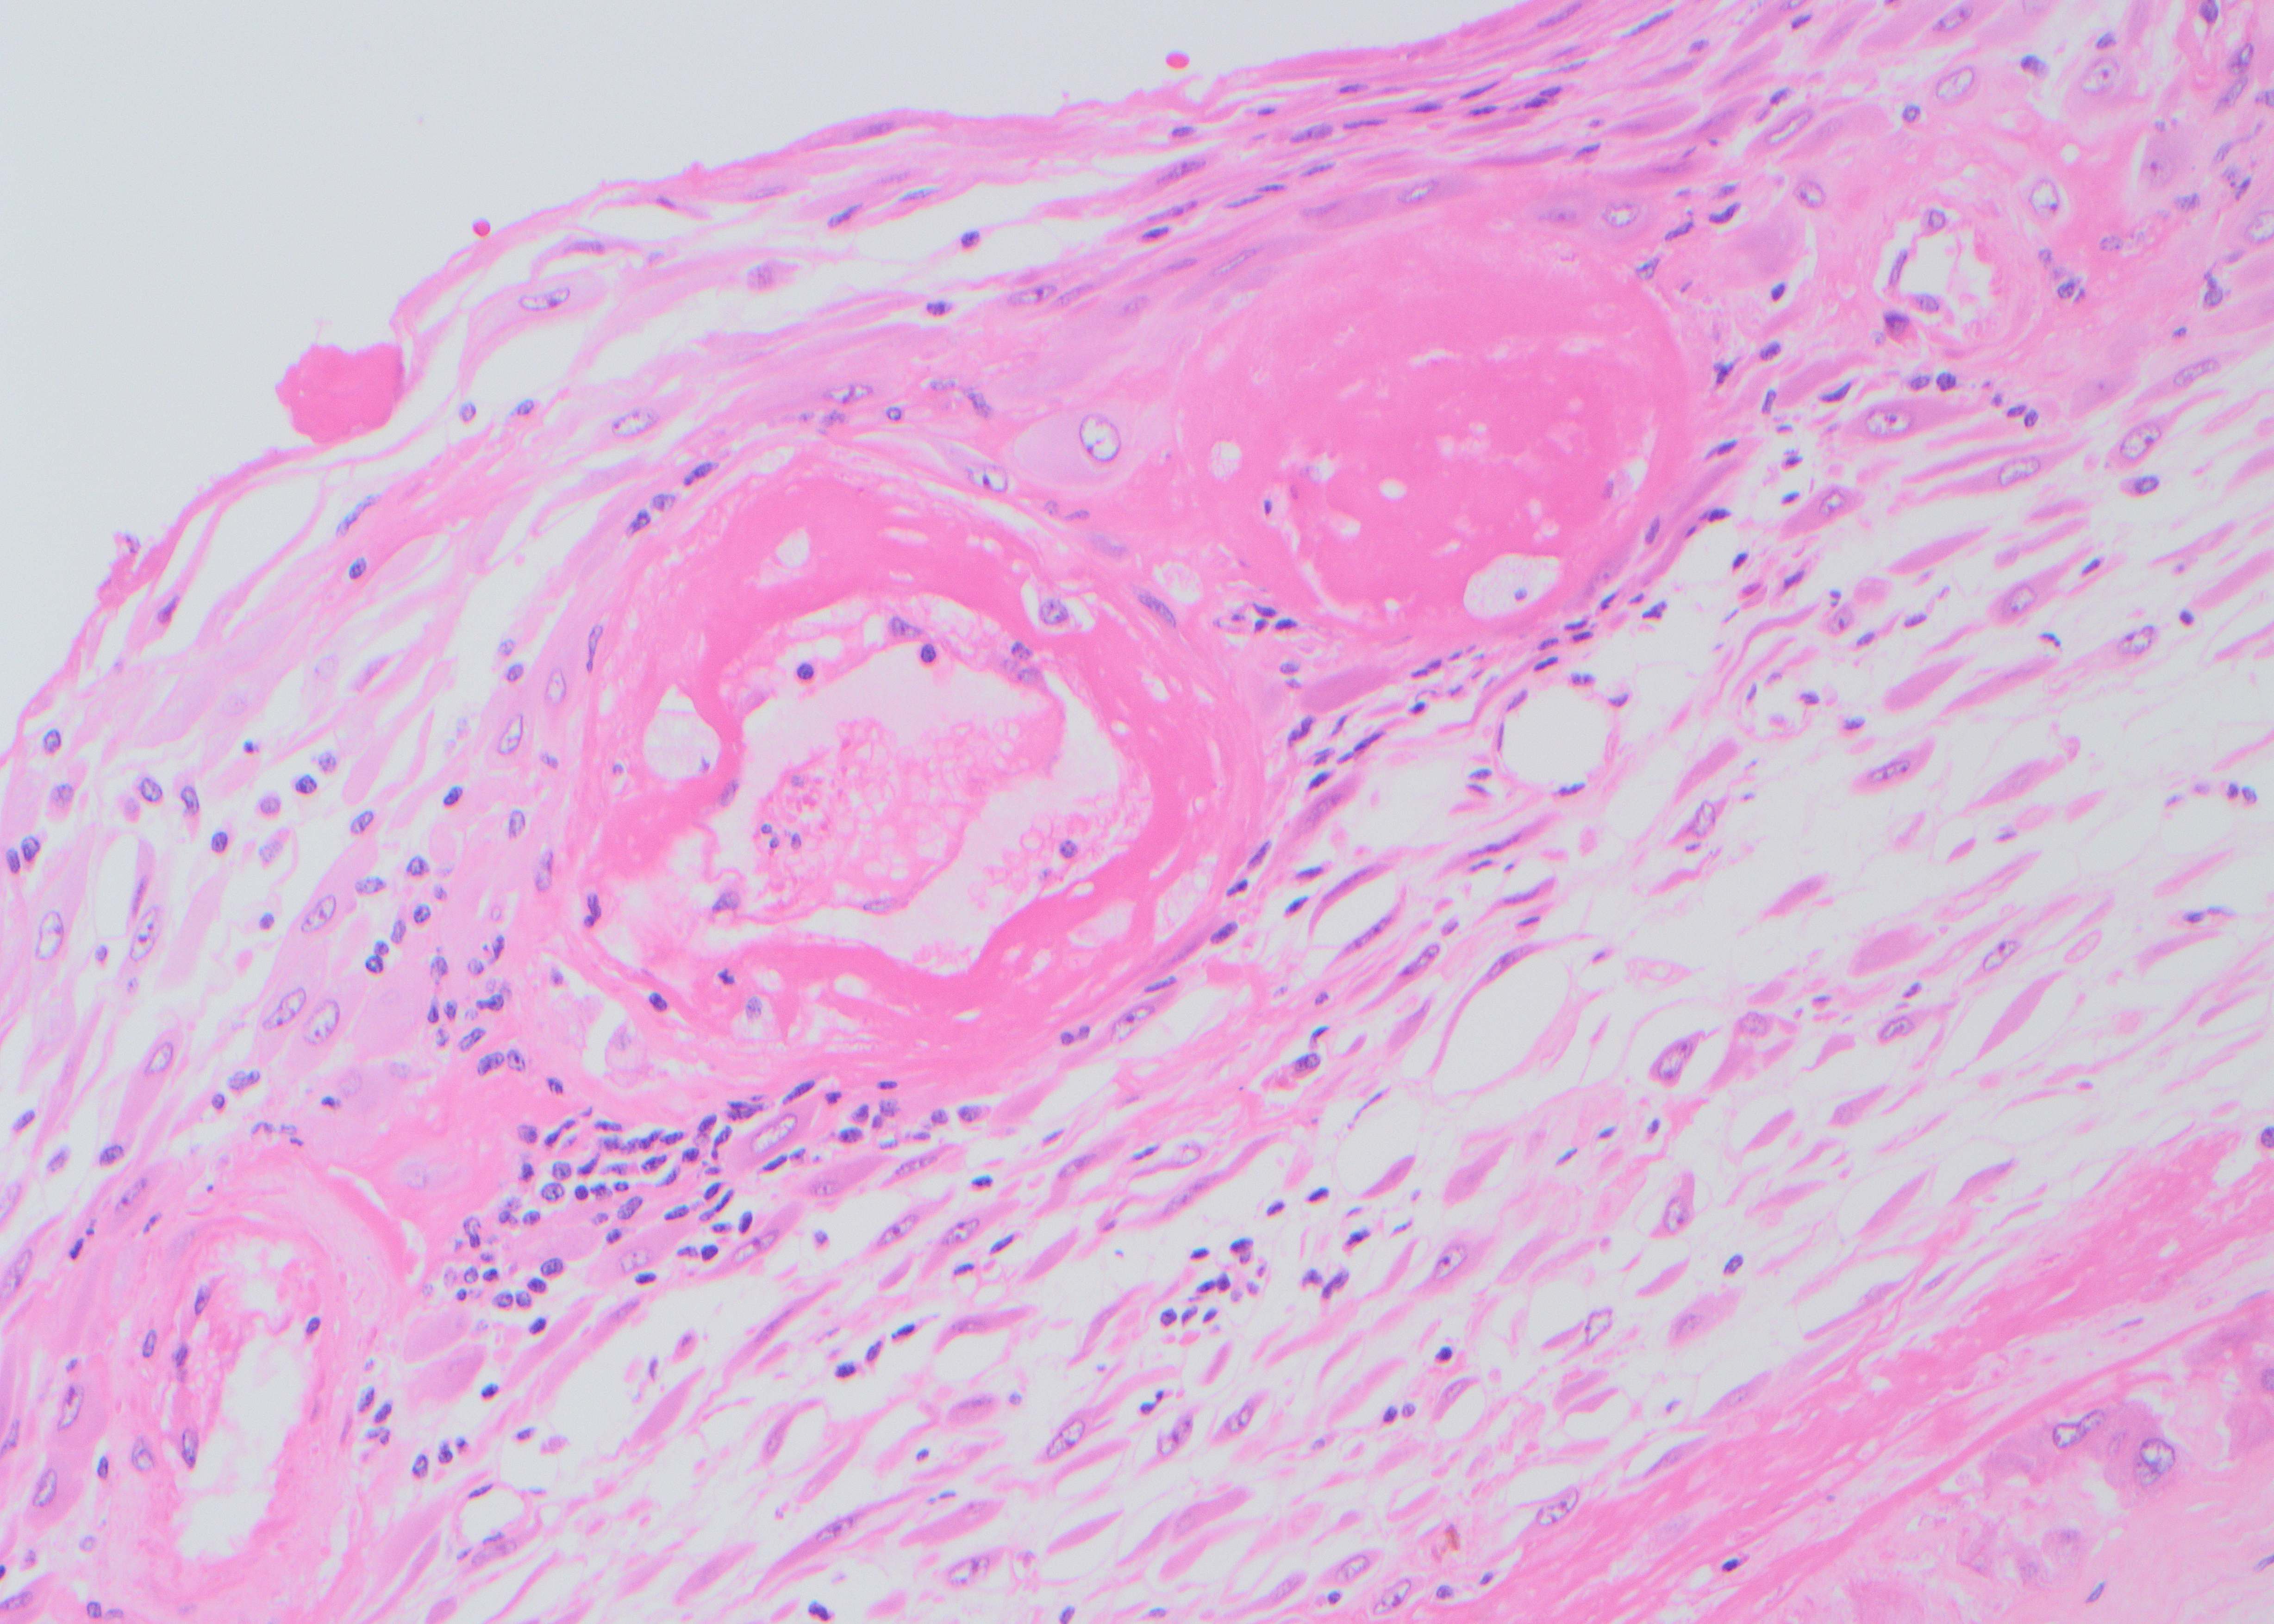

Case History:

A male patient in his mid-thirties with a personal and family history of polyps underwent duodenal polypectomy.